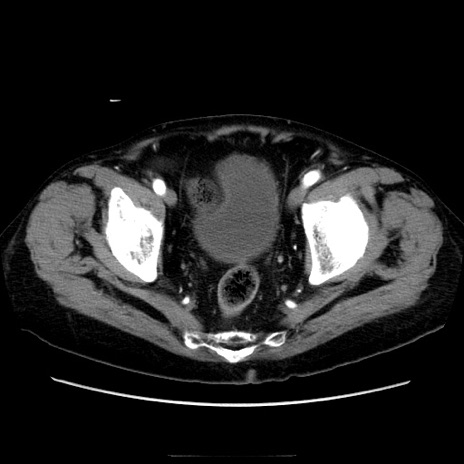

症例21(横断像)

【症例】70歳代男性

【主訴】腹痛

【現病歴】肝硬変・肝細胞癌にてかかりつけの方。約9時間前に食後より腹痛出現。症状が徐々に増悪し、嘔吐出現したため来院。

【既往歴】肝硬変、肝細胞癌(RFA、TACE後)

【身体所見】意識清明、表情苦悶様、BT 36℃、BP 129/78mmHg、P 88bpm、SpO2 97%(RA)、右上腹部から心窩部にかけて圧痛あり、反跳痛なし、筋性防御あり。

【データ】WBC 5800、CRP 0.16